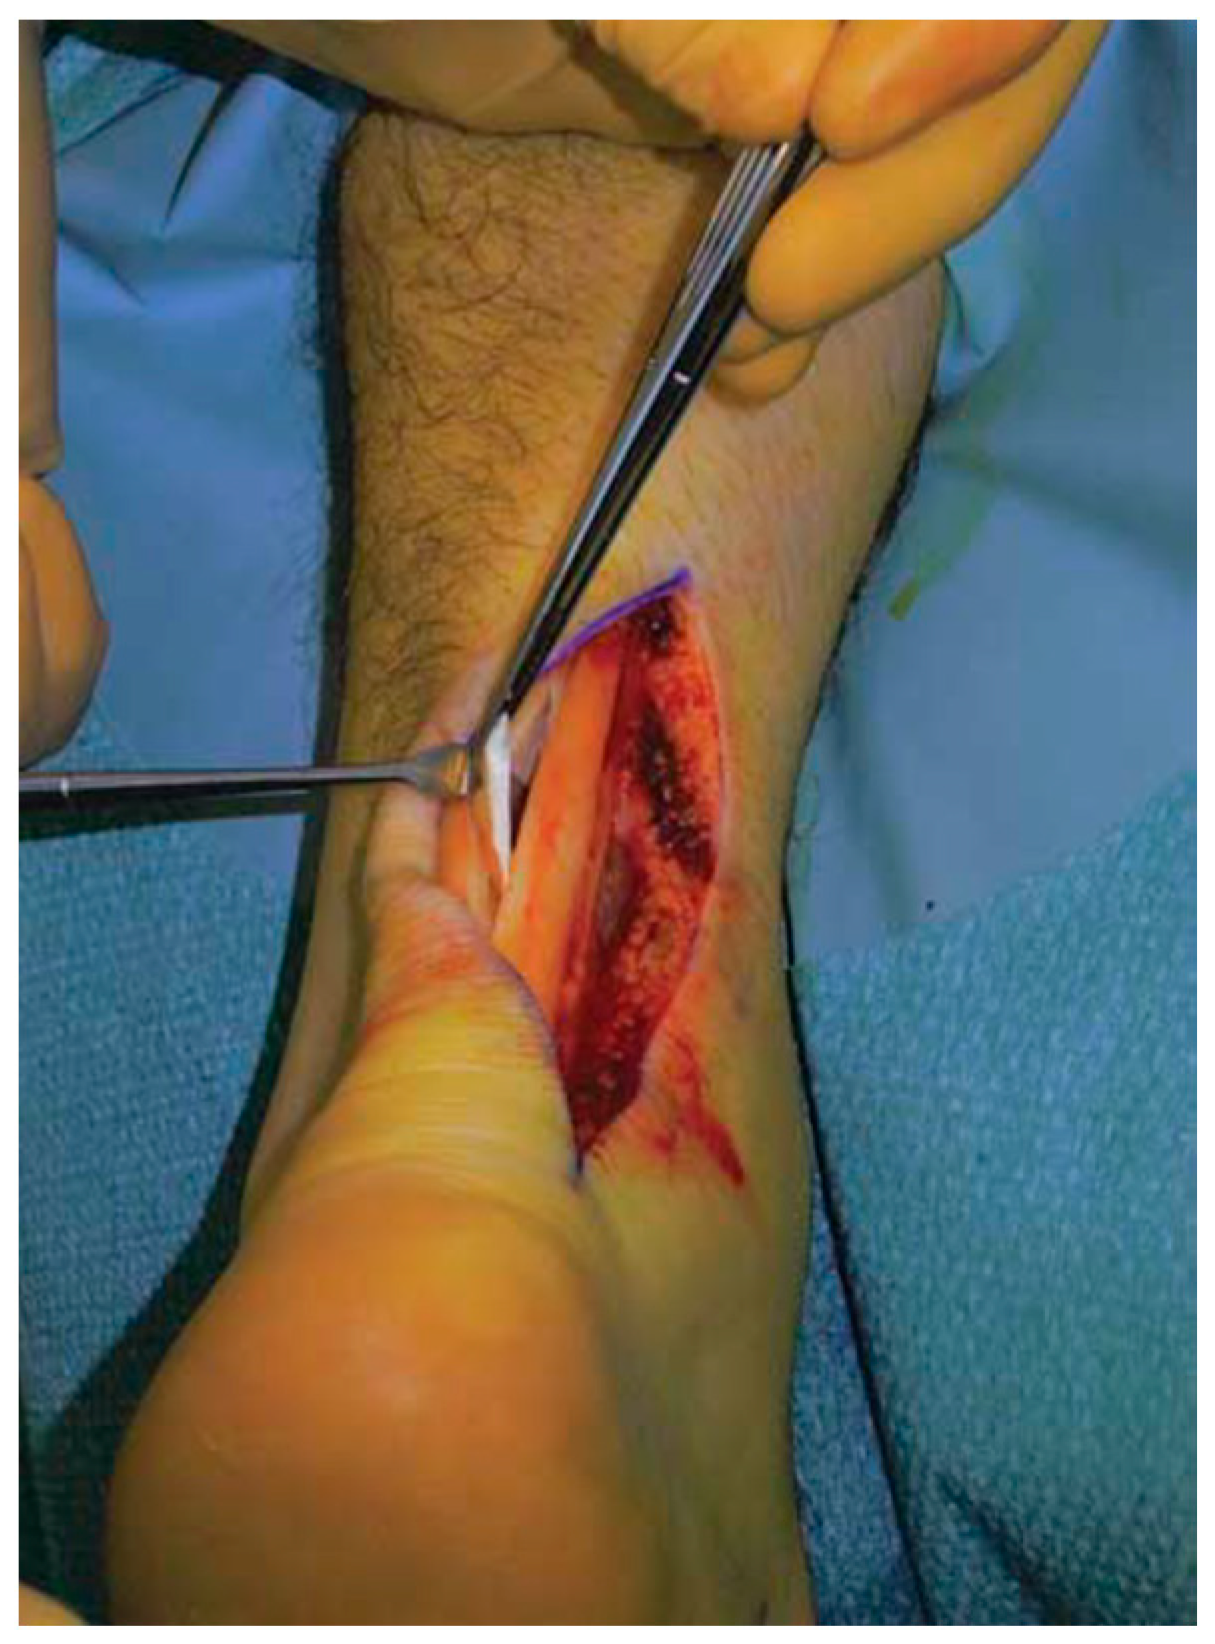

Good results have been reported for open surgery, with a success rate between 50% and 100% [121,122,123,124], removing the intra-tendinous lesions and more than 50% of tendon debrided (Figure 6).

Figure 6.

Open surgery for tendinopathy of the main body of the Achilles tendon. The tendinopathic tissue is identified and then excised.

Longitudinal incisions are made from tendon medial size avoiding sural nerve and short saphenous vein injuries [18]. Tendinopathic tissue is identified and removed, and it appear with a disorganised fibre bundles with a “crabmeat” appearance [18]. Any gap can be repaired using a side-to-side repair and can remain unsutured, or if significant loss tissue occurs, a tendon augmentation or transfer can be considered. Peroneus brevis (Figure 7) or flexor hallux longus (Figure 8) tendons are the most frequently used local tendon grafts [43,125,126].